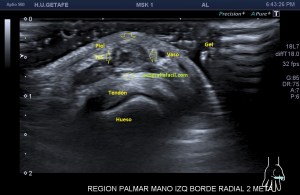

El paciente del caso que te expongo hoy como primer post del 2021 es un paciente de uno 40 años que nota desde hace un año un pequeño bultoma en la palma de la mano, en la región flexora en el eje largo del 2 dedo, a la altura de la articulación metacarpofalángica, ligeramente radial, viene referido del traumatólogo.

En mi interrogatorio habitual el paciente descarta traumatismo, no recuerda, ligero crecimiento sin dolor. Al tocar el bulto para localizarlo, lo primero que me llama la atención es que tiene pulso, muy evidente, es duro y muy pequeño, pero el pulso es muy evidente, no había coloración cutánea. El paciente ni el médico refirieron este dato superimportante (el latido) que dirigió el estudio absolutamente, como ves en la imágenes.

Escojo la sonda de ultraalta frecuencia, 18 mHz, y ajusto los parámetros para realizar un estudio con la intención de encontrar algo muy superficial, por supuesto, gran cantidad de gel, nada de presión, apoyo levemente el transductor.

1

En esta primera imagen me encuentro, primero, un estructura heterogénea, redonda, ligeramente ovalada con un centro anecoico y un halo grueso e hipoecogénico.

Lo segundo es delimitarla bien, tener bien estudiada la anatomía de referencia, imagen 2, respecto de la ecoestructura patológica y su propia ecoarquitectura. Por supuesto aplicamos el protocolo de referencia, localización, estudio, medición y vascularización que hoy ves resumido en estas 5 imágenes ya que el estudio lo enfoqué en el estudio de algo vascular.

2

La anatomía, tan importante siempre, buscando la relación, sobre todo, con el tendón al que claramente esta lesión no pertenecía ni afectaba.

3

El corte en eje largo como te indica el pictograma es muy importante, en teoría debería haber encontrado una estructura redondeada en eje corto y tubular en eje largo, como debiera corresponder a esta lesión vascular, pero los hallazgos no arrojaron dicha imagen.

Demostré el pulso en ambos ejes, pero no pude comprobar la estructura tubular en longitudinal…el motivo, el tamaño de la estructura y su gruesa pared que puedes apreciar en ambos ejes y que correspondía a una incremento de la pared del propio vaso, vaso que se encontraba parcialmente trombosado por este crecimiento de su pared, habitual en estas lesiones post traumáticas, donde el propio vaso sangra y esa sangre se colecciona alrededor el mismo.

Se demostró lo que ya presentía, que era la vascularización típica de un vaso, vaso que resultó ser uno de alto flujo, y  te explico…cuando estudiamos una malformación vascular por ecografía, podemos encontrarnos malformaciones de bajo flujo, las venas, de alto flujo, arterias o mixtos de ambas.

En la imagen 5 ves el típico aspecto de un vaso de alto flujo, lo normal, ya que tenía latido. Vas a ver dicho espectro con aspecto de picos y valles muy marcados, el sonido también es diferencial, puedes ver el doppler espectral y escucharlo. Su sonido y su aspecto es distinto del de una vena.

En este caso debí usar una muestra, flecha amarilla de la imagen 5, lo más pequeña posible, ya que el vaso lo era igual, adaptaremos esta muestra al tamaño del vaso que quieras estudiar. si la muestra no es la idónea la lectura puede ser incoherente. La muestra es el tamaño del «roi2 que hará el registro de la zona a estudio. Te enlazo arriba para que revises nociones básicas de doppler en post anteriores, también puedes consultar el índice del blog al final de este Post.

En este vídeo puedes ver como en la imagen 2D  como late la estructura, y como con el doppler color la vascularización es evidente. Puedes estudiarlo con Triplex, en el enlace a instagram ves como se estudia la lesión con una técnica de la que ya te he hablado más veces, donde puedes ver el doppler color y el espectral a la vez, eso sí, consumieno muchos recursos del equipo.

El diagnóstico final del radiólogo fue psudoaneurisma de la arteria palmar del segundo dedo.